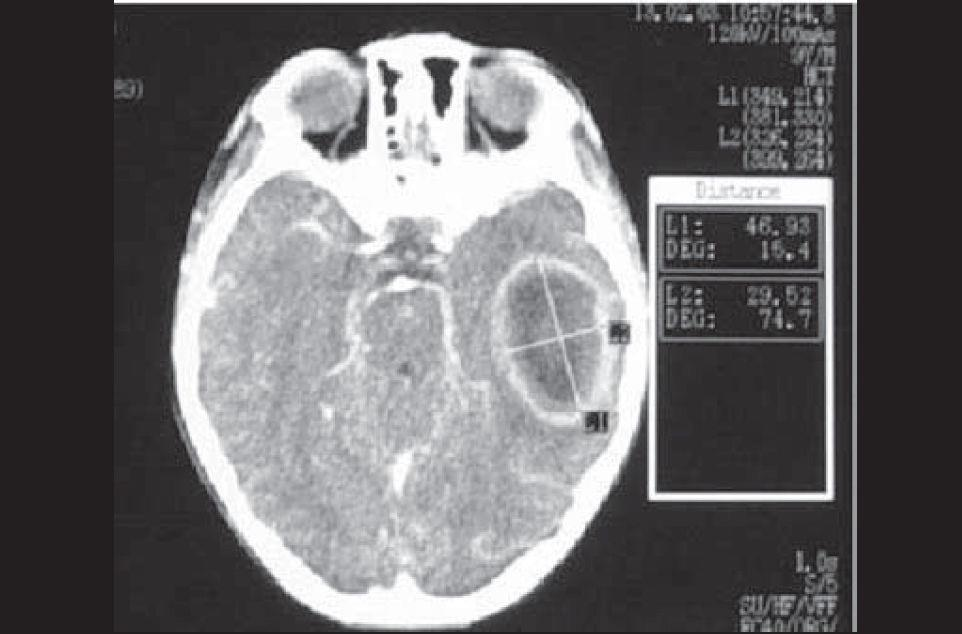

Cerebral Abscess

A 2-year-old child with vomiting, fever, and change in level of consciousness. The child had a visit to ER 2 weeks ago for acute otitis media but the mother didnโt give the medication.

CT Scan Finding

- Cerebral Abscess.

Usual Location

- Temporal lobe.